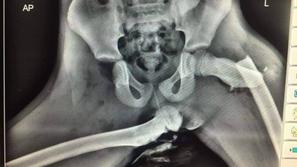

Razvada Samo pokažite mu to fotografijo ... Šokantna rentgenska fotografija izpahnjene stegnenice, posledica nespametnega početja.

Huda poškodba Vonnova ne izgleda najbolje Najuspešnejša alpska smučarka vseh časov je po padcu med treningom na Copper Mountainu spet legla na kirurško mizo.